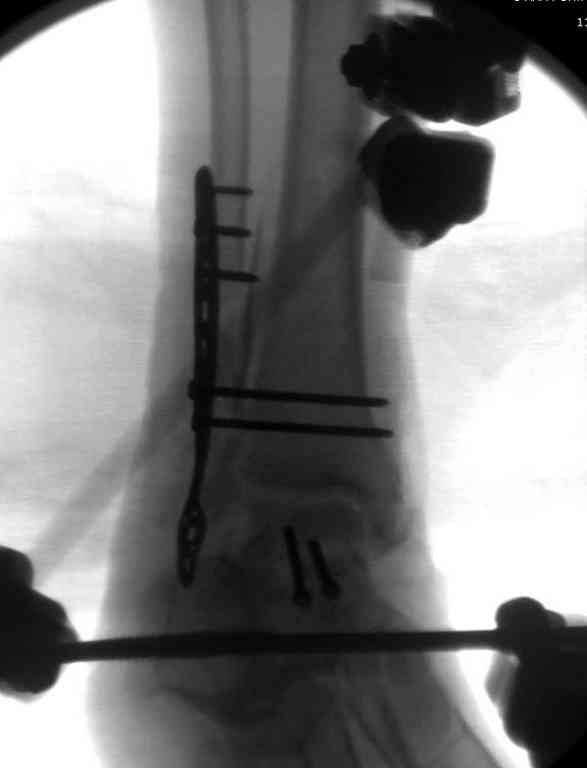

Здесь на фото примеры:

Переломовывих тарана с повреждением медиальной стороны. Через 4 часа после поступления проведена репозиция и фиксация тарана после Irrigation&Debridment. Частичное несращение медиальной лодыжки не беспокоит, вернулся к активному образу жизни. Полная нагрузка разрешена через 11 недель. Финальные снимки через 11 месяцев.

Второй случай прооперирован вчера.

10 дней назад поступил с открытым повреждением медиальной лодыжки и переломо вывихом таранной кости. Ургентно сделана репозиция с наложением наружного фиксатора + Irrigation&Debridment.

Во время репозиции выявили повреждение заднего сухожилия м. тибиалис и задней большеберцовой артерии. Медиальную рану удалось закрыть частично и установлен вакуум.

Дважды провели Irrigation&Debridment с заменой вакуума.

Вчера провели фиксацию.

Из-за многооскольчатости дистальной части малоберцовой, где невозможно было провести фиксацию шурупами, перелом зафиксирован подпирающей пластиной, которая должна служить дополнением отсутствующей дистальной части малоберцовой (lateral cortex substitute).

Для стабильности два шурупа на синдесмоз.

Медиальную рану с приближенными краями продолжаем вакуумировать (KCI). Наружный фиксатор оставлен на пару недель, надеюсь, небольшая рана будет гранулировать и закроется без кожной пластики. Фиксация медиальной ложыжки не планируется.